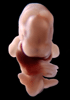

Carnegie Stage 17 (41 post-ovulatory days)

Most embryos at stage 17 are approximately 41 postovulatory days old and measure 11-14 mm in length. Distinguishing criteria for this stage include distinct digital rays in the hand plate, a rounded digital plate in the foot, a complete complement of hillocks on the mandibular and hyoid arches, distinct nasofrontal grooves, and a slight indication of a lumbar curvature.

This specimen does not represent normal development. The caudal nueral tube has failed to close properly.